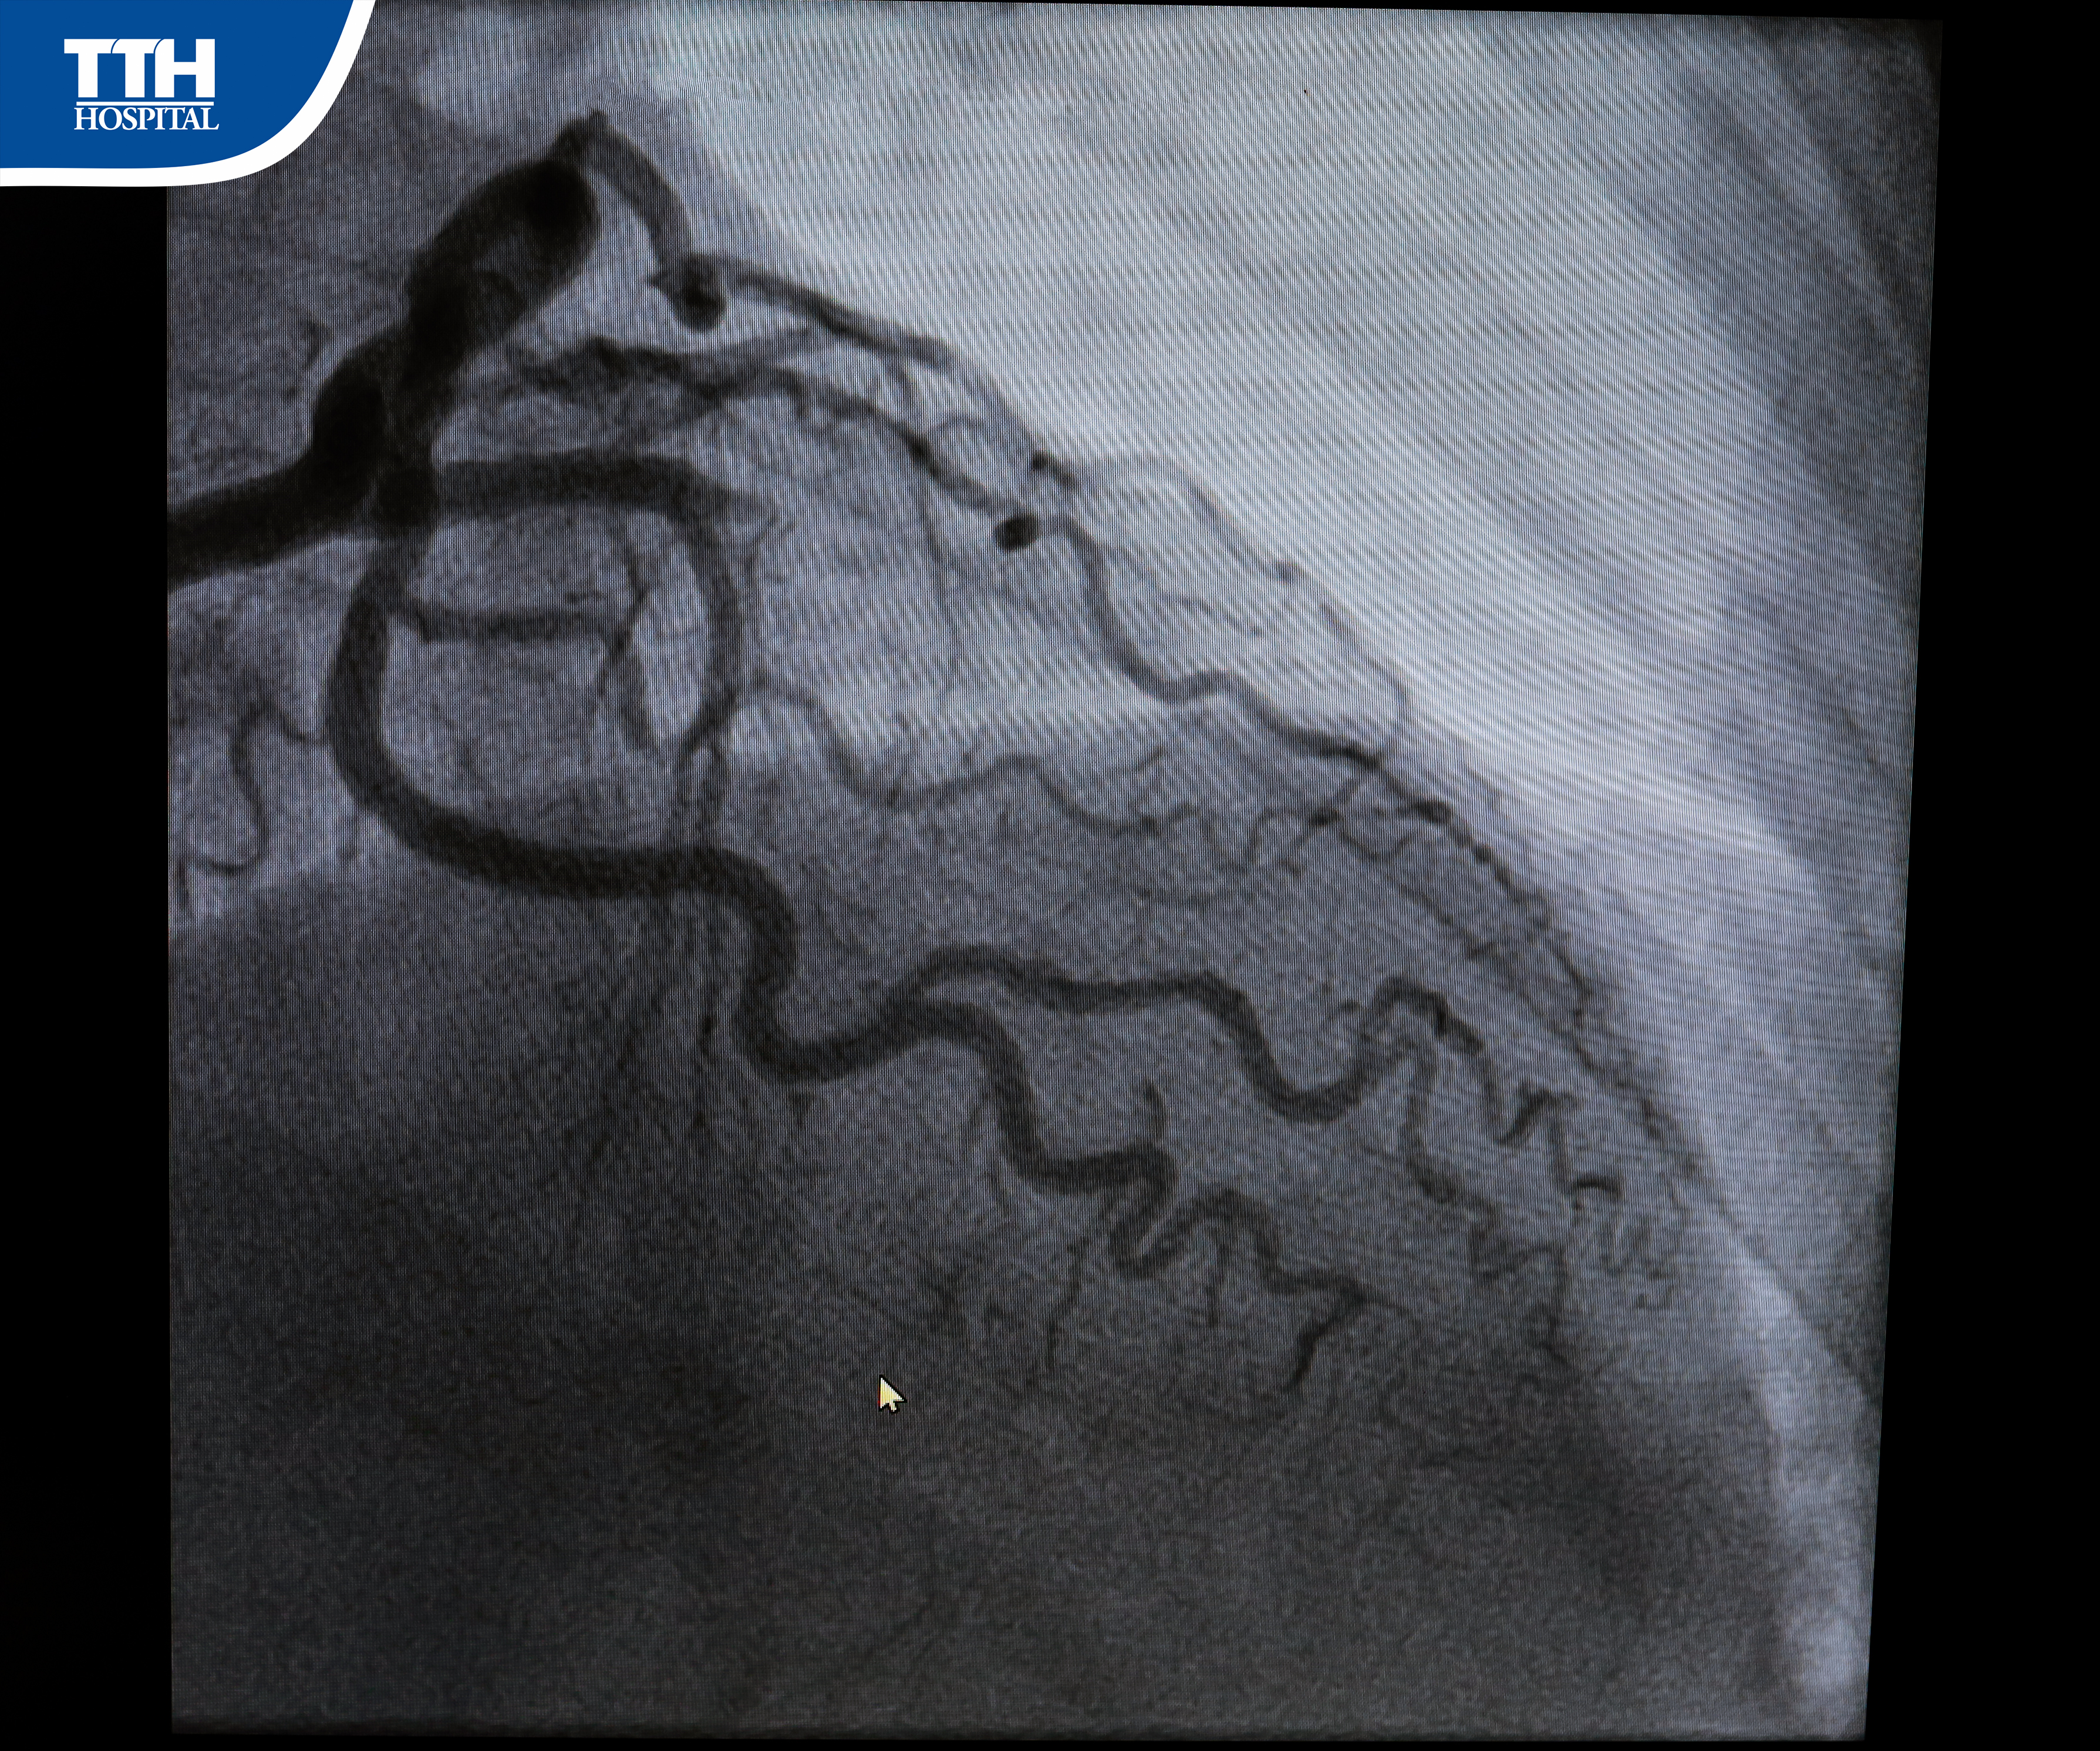

🌟 Tại Trung tâm Can thiệp Tim mạch – BVĐK TTH Hà Tĩnh, kết quả thăm khám và chụp mạch vành cho thấy tắc hoàn toàn động mạch liên thất trước (LAD) – tình trạng nguy cơ rất cao gây biến chứng nghiêm trọng. Nhận thấy cần xử trí khẩn cấp, ê-kíp can thiệp đã nhanh chóng đặt stent tái thông mạch máu.

🔎 Thủ thuật diễn ra thuận lợi, bệnh nhân hết đau ngực, không còn khó thở. Sau 7 ngày, điều trị, can thiệp mạch vành và theo dõi, bà xuất viện với sức khỏe ổn định, trở lại sinh hoạt bình thường.